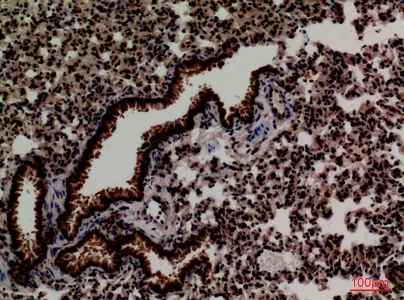

MPO Rabbit Polyclonal Antibody

Cat: APRab14056